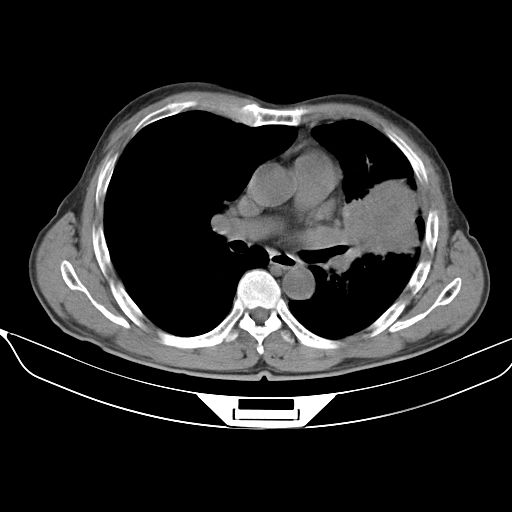

以下是引用shuiyuan在2010-3-1 10:45:00的发言:[br]考虑左肺上叶中心型肺癌伴阻塞型炎症,邻近胸膜受侵。

以下是引用心路寻觅在2010-3-1 10:23:00的发言:[br]1、考虑左肺上叶周围型肺癌[br]2、右上肺陈旧性病灶。[br][br][本贴已被 心路寻觅 于 2010-3-1 10:40:18 修改过]